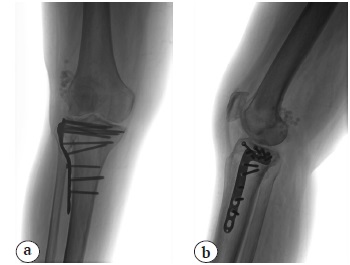

В последующем пациентка находилась под наблюдением врача-травматолога амбулаторной службы. Цементный спейсер удален в срок 5 мес. после травмы, через 3,5 мес. после его постановки (рис. 6). После снятия гипсовой иммобилизации пациентка занималась лечебной физкультурой, постепенно расширяла двигательный режим. Эпизодов обострения инфекции не было.

Рис. 6. Рентгенограммы правого коленного сустава через 5 мес. после травмы, снятия гипсовой иммобилизации и удаления цементного спейсера: a — прямая проекция; b — боковая проекция

Fig. 6. X-rays of the right knee 5 months after injury, removal of the cast and cement spacer: a — AP view; b — lateral view

Пациентка осмотрена в срок 2 года после операции. Она не предъявляет жалоб на боль и отеки, ощущение нестабильности в области коленного сустава, пользуется тростью только при ходьбе на длительные расстояния, самостоятельно поднимается и спускается по лестнице. Объем движений в коленном суставе ограничен незначительно. Сгибание в коленном суставе до 80°, разгибание — 175°. Функциональная оценка по шкале Lysholm составила 79 баллов, по шкале KSS — 80 баллов (рис. 7).

Рис. 7. Рентгенологический результат лечения через 2 года после операции: a — прямая проекция; b — боковая проекция

Fig. 7. X-rays outcome of the treatment, 2 years after surgery: a — AP view; b — lateral view